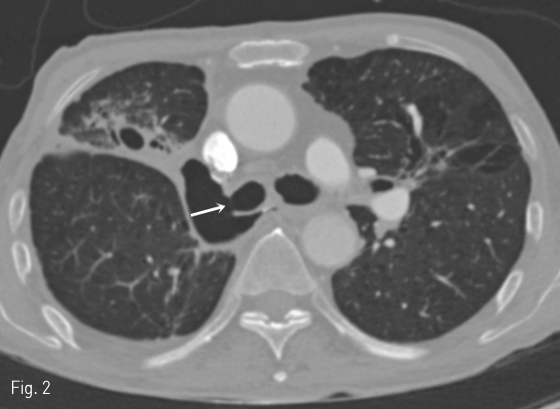

호흡기내과의 협진 하에 기관지내시경을 우주기관지 (right main bronchus)에 거치하였고 우상엽 절제부위의 기관흉막루를 확인하였다 (Fig. 3). 기관지 내시경 내로 0.035인치의 뻣뻣한 유도철사(Radifocus Guidewire stiff type, Terumo Medical Corp., Somersen NJ, USA)의 끝을 투시 유도 하에 우하엽 기관지에 위치시켰다. 그리고 유도철사의 끝을 우하엽 기관지에 유지시킨 상태로 기관지 내시경을 탈거하였다. 그 후 투시 유도하에 18 mm x 4 cm retrievable self-expanding silicone-covered stent (Hercules airway stent, S & G Biotech, Seongnam, Korea)를 우주기관지(right main bronchus)에 설치하였다. 스텐트 설치시 기관흉막 루가 완전히 덮이면서도 근위부가 기관 내로 돌출되지 않고 (Fig. 4) 원위부가 우폐의 다른 엽기관지를 막지 않도록 주의하였다. 시술 직후 기관지 내시경으로 기관흉막루가 stent로 완전히 덮인 것과 우폐의 다른 엽기관지들이 막히지 않은 것을 확인하였다 (Fig. 5).

Fig 4

The covered self-expanding stent is being deployed in the right main bronchus. Caution was taken that the proximal end of the stent would not protrude into the trachea.